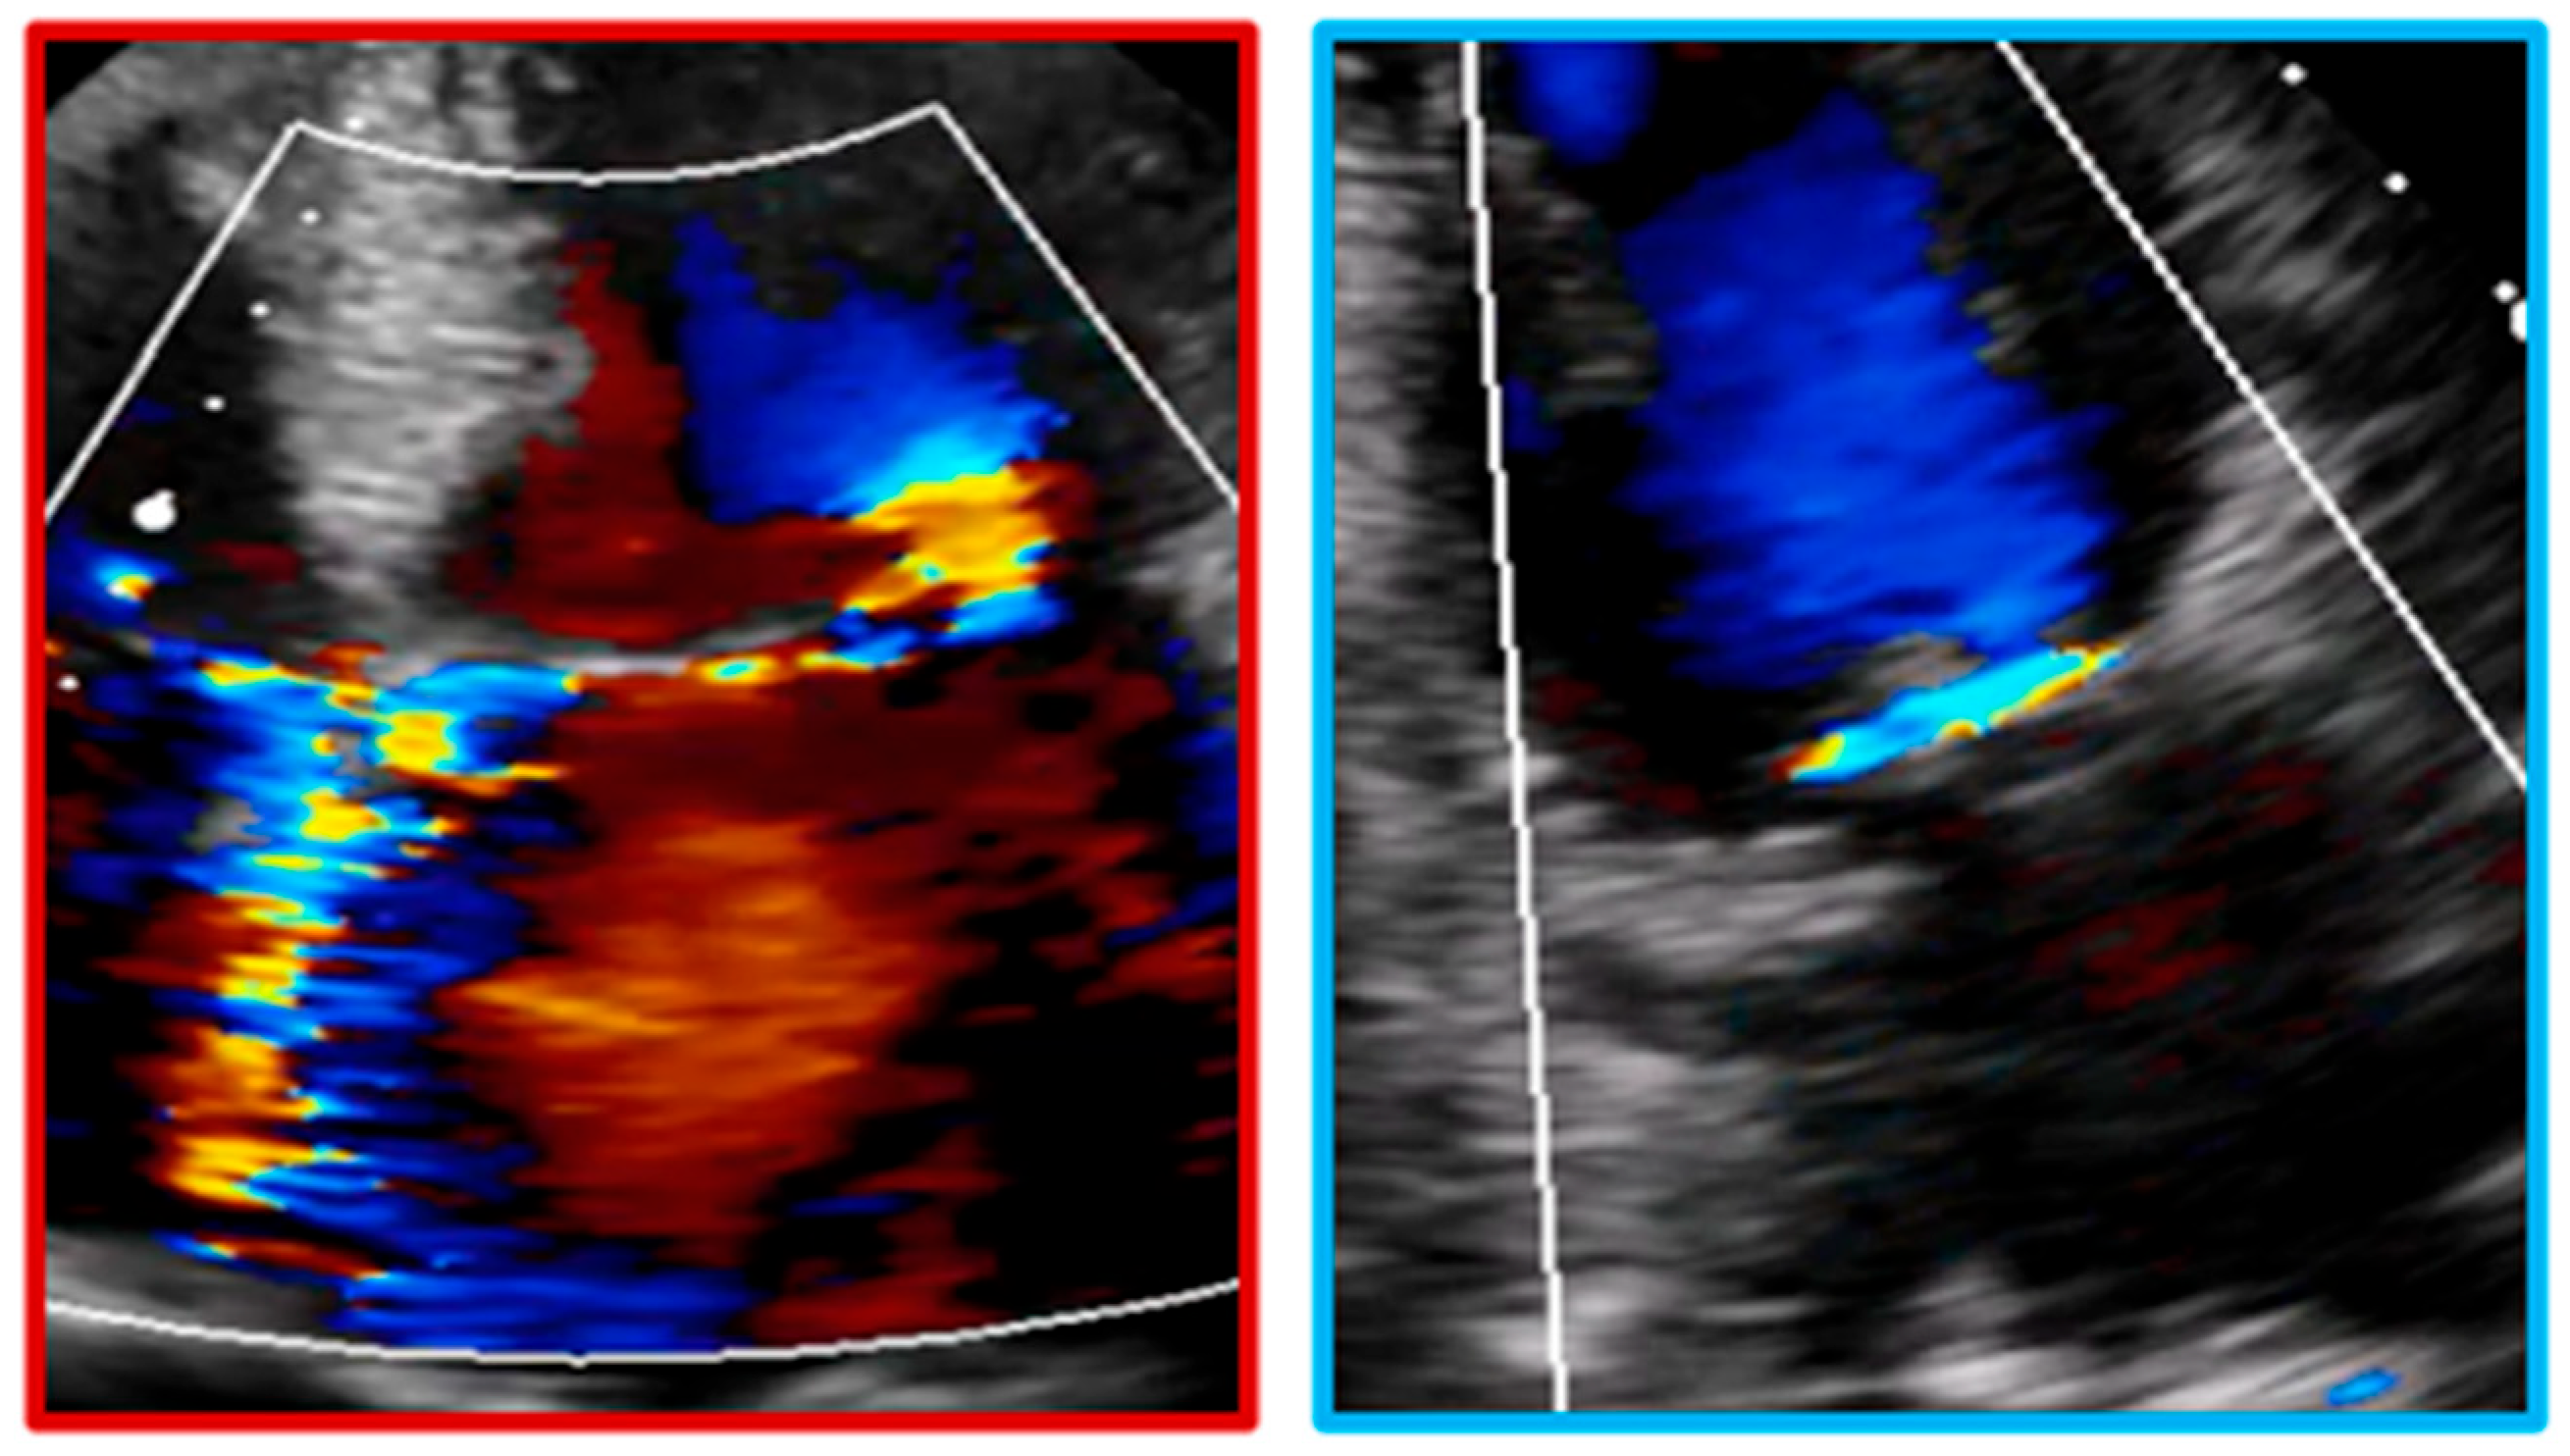

- Wiener, P.C.; Friend, E.J.; Bhargav, R.; Radhakrishnan, K.; Kadem, L.; Pressman, G.S. Color Doppler Splay: A Clue to the Presence of Significant Mitral Regurgitation. J. Am. Soc. Echocardiogr. 2020, 33, 1212–1219.e1. [Google Scholar] [CrossRef]